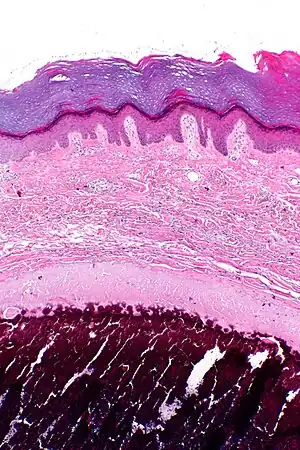

| Micrograph of calcinosis cutis. The calcification is purple (bottom of image). H&E stain. | |

Calcinosis cutis is a type of calcinosis wherein calcium deposits form in the skin. A variety of factors can result in this condition. The most common source is dystrophic calcification, which occurs in soft tissue as a response to injury. In addition, calcinosis is seen in Limited Cutaneous Systemic Sclerosis, also known as CREST syndrome (the "C" in CREST). In dogs, calcinosis cutis is found in young, large breed dogs and is thought to occur after a traumatic injury.